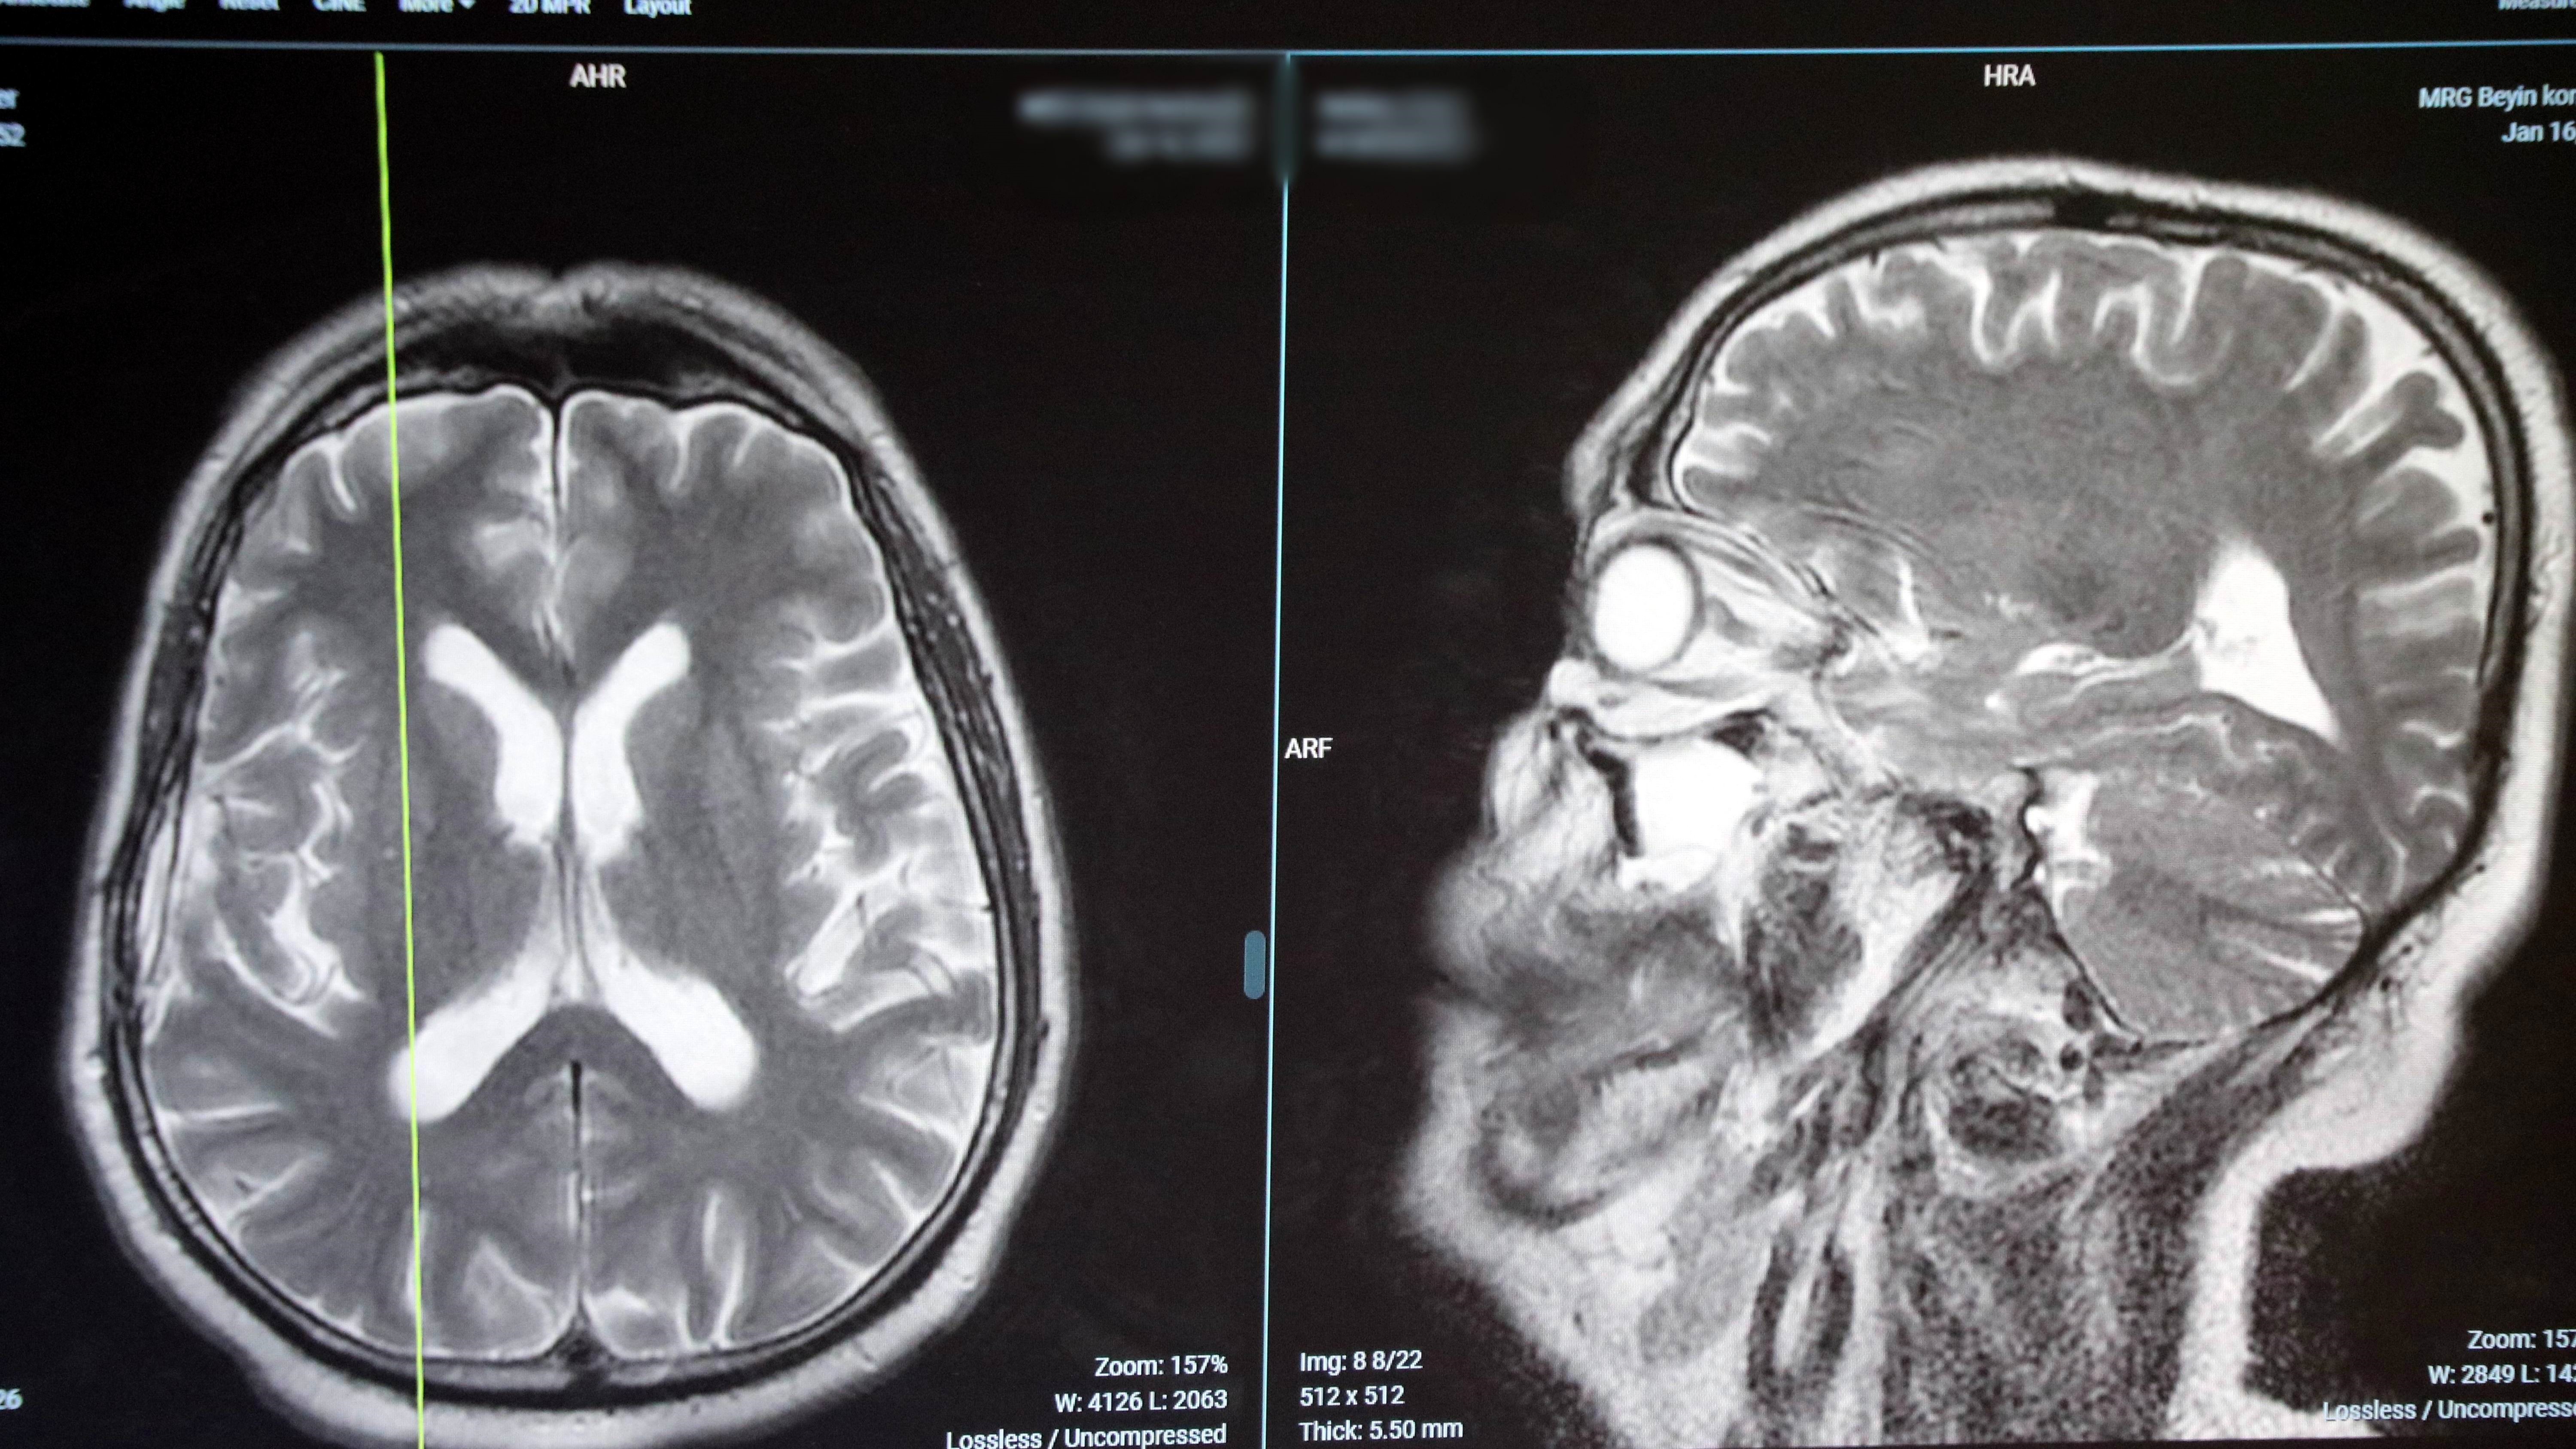

Bazı beyin tümörlerinin hastanın sağlığına olumsuz etki etmediğini belirten Enis Kuruoğlu, “Hastada tümör tespit ettiğimizde radyolojik olarak da iyi huylu olup olmadığını gözlemliyoruz. Eğer tümör fazla büyük değilse ve hastanın sağlığına risk oluşturmuyorsa 5-10 yıl sonra cerrahi uygulamadan takip yapabiliyoruz. Tümörde büyüme olursa çıkartılabiliyor. Kötü huylu tümörlerde ise geç kalınmaması gerekiyor. Hastada tümör tespit edildiği zaman mutlaka patolojik tanı alınması gerekiyor. Hatta tümör çıkarılabilecek gibi ise çıkarılması gerekiyor. Tümör kötü bir yerde, çıkarılması imkansız bir yerde ise, hasta ameliyattan sonra yatağa bağımlı kalacak, bilincini kaybedecekse küçük bir biyopsi alıp tümörün adını koyarak tedavi yöntemini belirliyoruz. Bunlara da ışın, gamma knife (odaklanmış ışınların hedef dokuya tek bir seferde verilmesi), kemoterapi tedavileri yapılabiliyor. Gelişen teknoloji ile birlikte kötü huylu tümörlerde de çok iyi sonuçlar alabiliyoruz” ifadelerini kullandı.